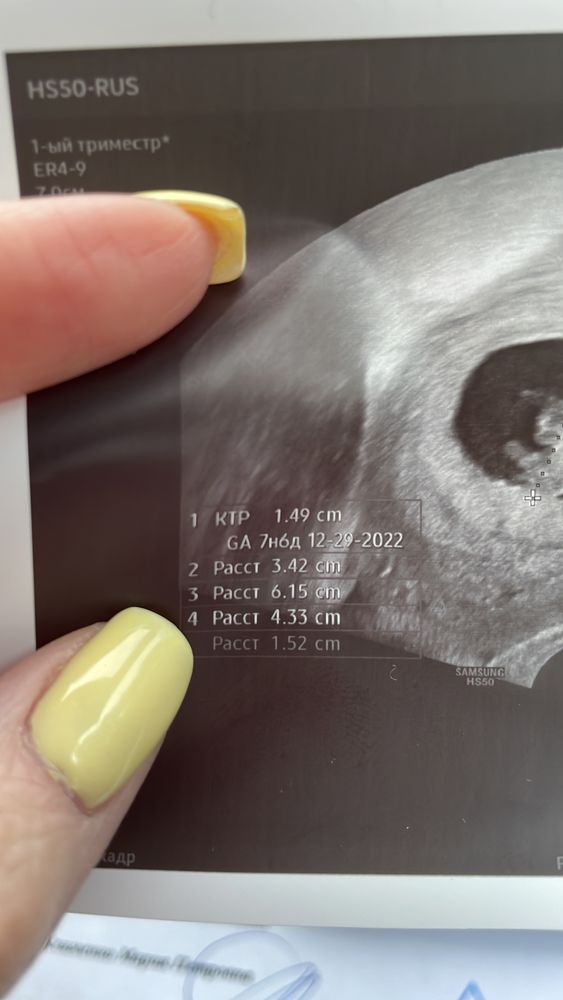

КТР= 15мм (7нед.6 дней) , чсс 163 у/мин🥰 на узи пдр 29.12.2022 увидела. А ещё скрин моего предсказания в новогоднюю ночь в инстаграме) вот тебе и сюрприз)